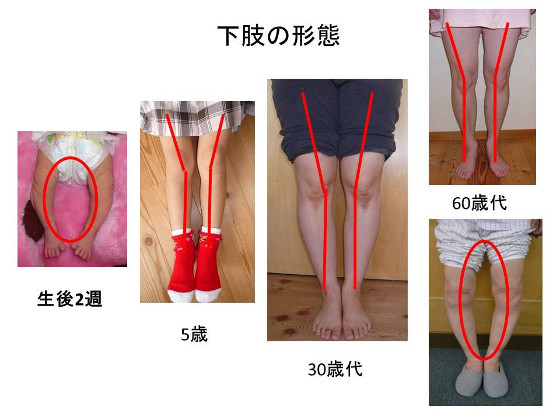

最新デザインの 膝関節の難治性病態に対する手術―日常診療で困ったときのこの一 医学一般